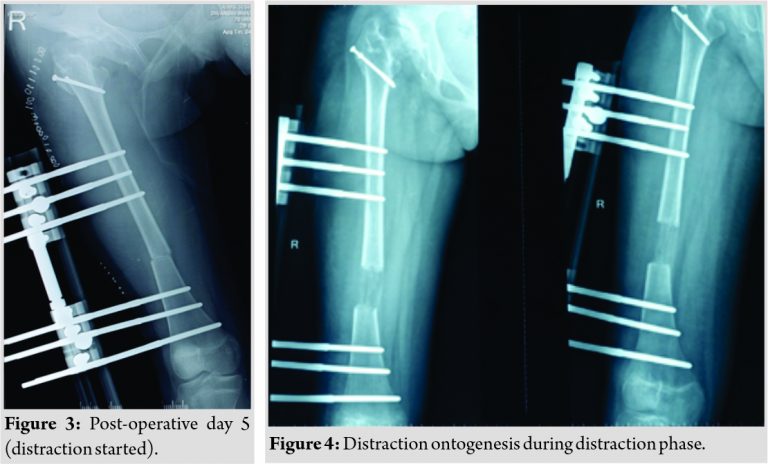

Care was taken to preserve the piriformis attachment on to main femoral fragment. With the help of patella holding clamp, the GT fragment was held and shifted to 2 cm distally and fixed with two 4 mm cannulated cancellous screws. The wound was closed over the suction drain and the patient was then planned for monorail external fixator in the supine position. Gradual distraction was started from the 5th post-operative day (Fig. 3).

Careful follow-up evaluation was done and distraction was stopped once limb length equalization was achieved (Fig. 4-6). The fixator was removed after 112 days. The patient had no complication postoperatively except mild pain during early phases of distraction which was managed with high-dose analgesics and knee stiffness in the later part of the distraction. She achieved a complete range of motion of knee with extensive physiotherapy and quadriceps strengthening exercises. At final follow-up of 6 months, the patient had no equinus at the ankle with improvement in hip abduction with minimal abductor lurch.